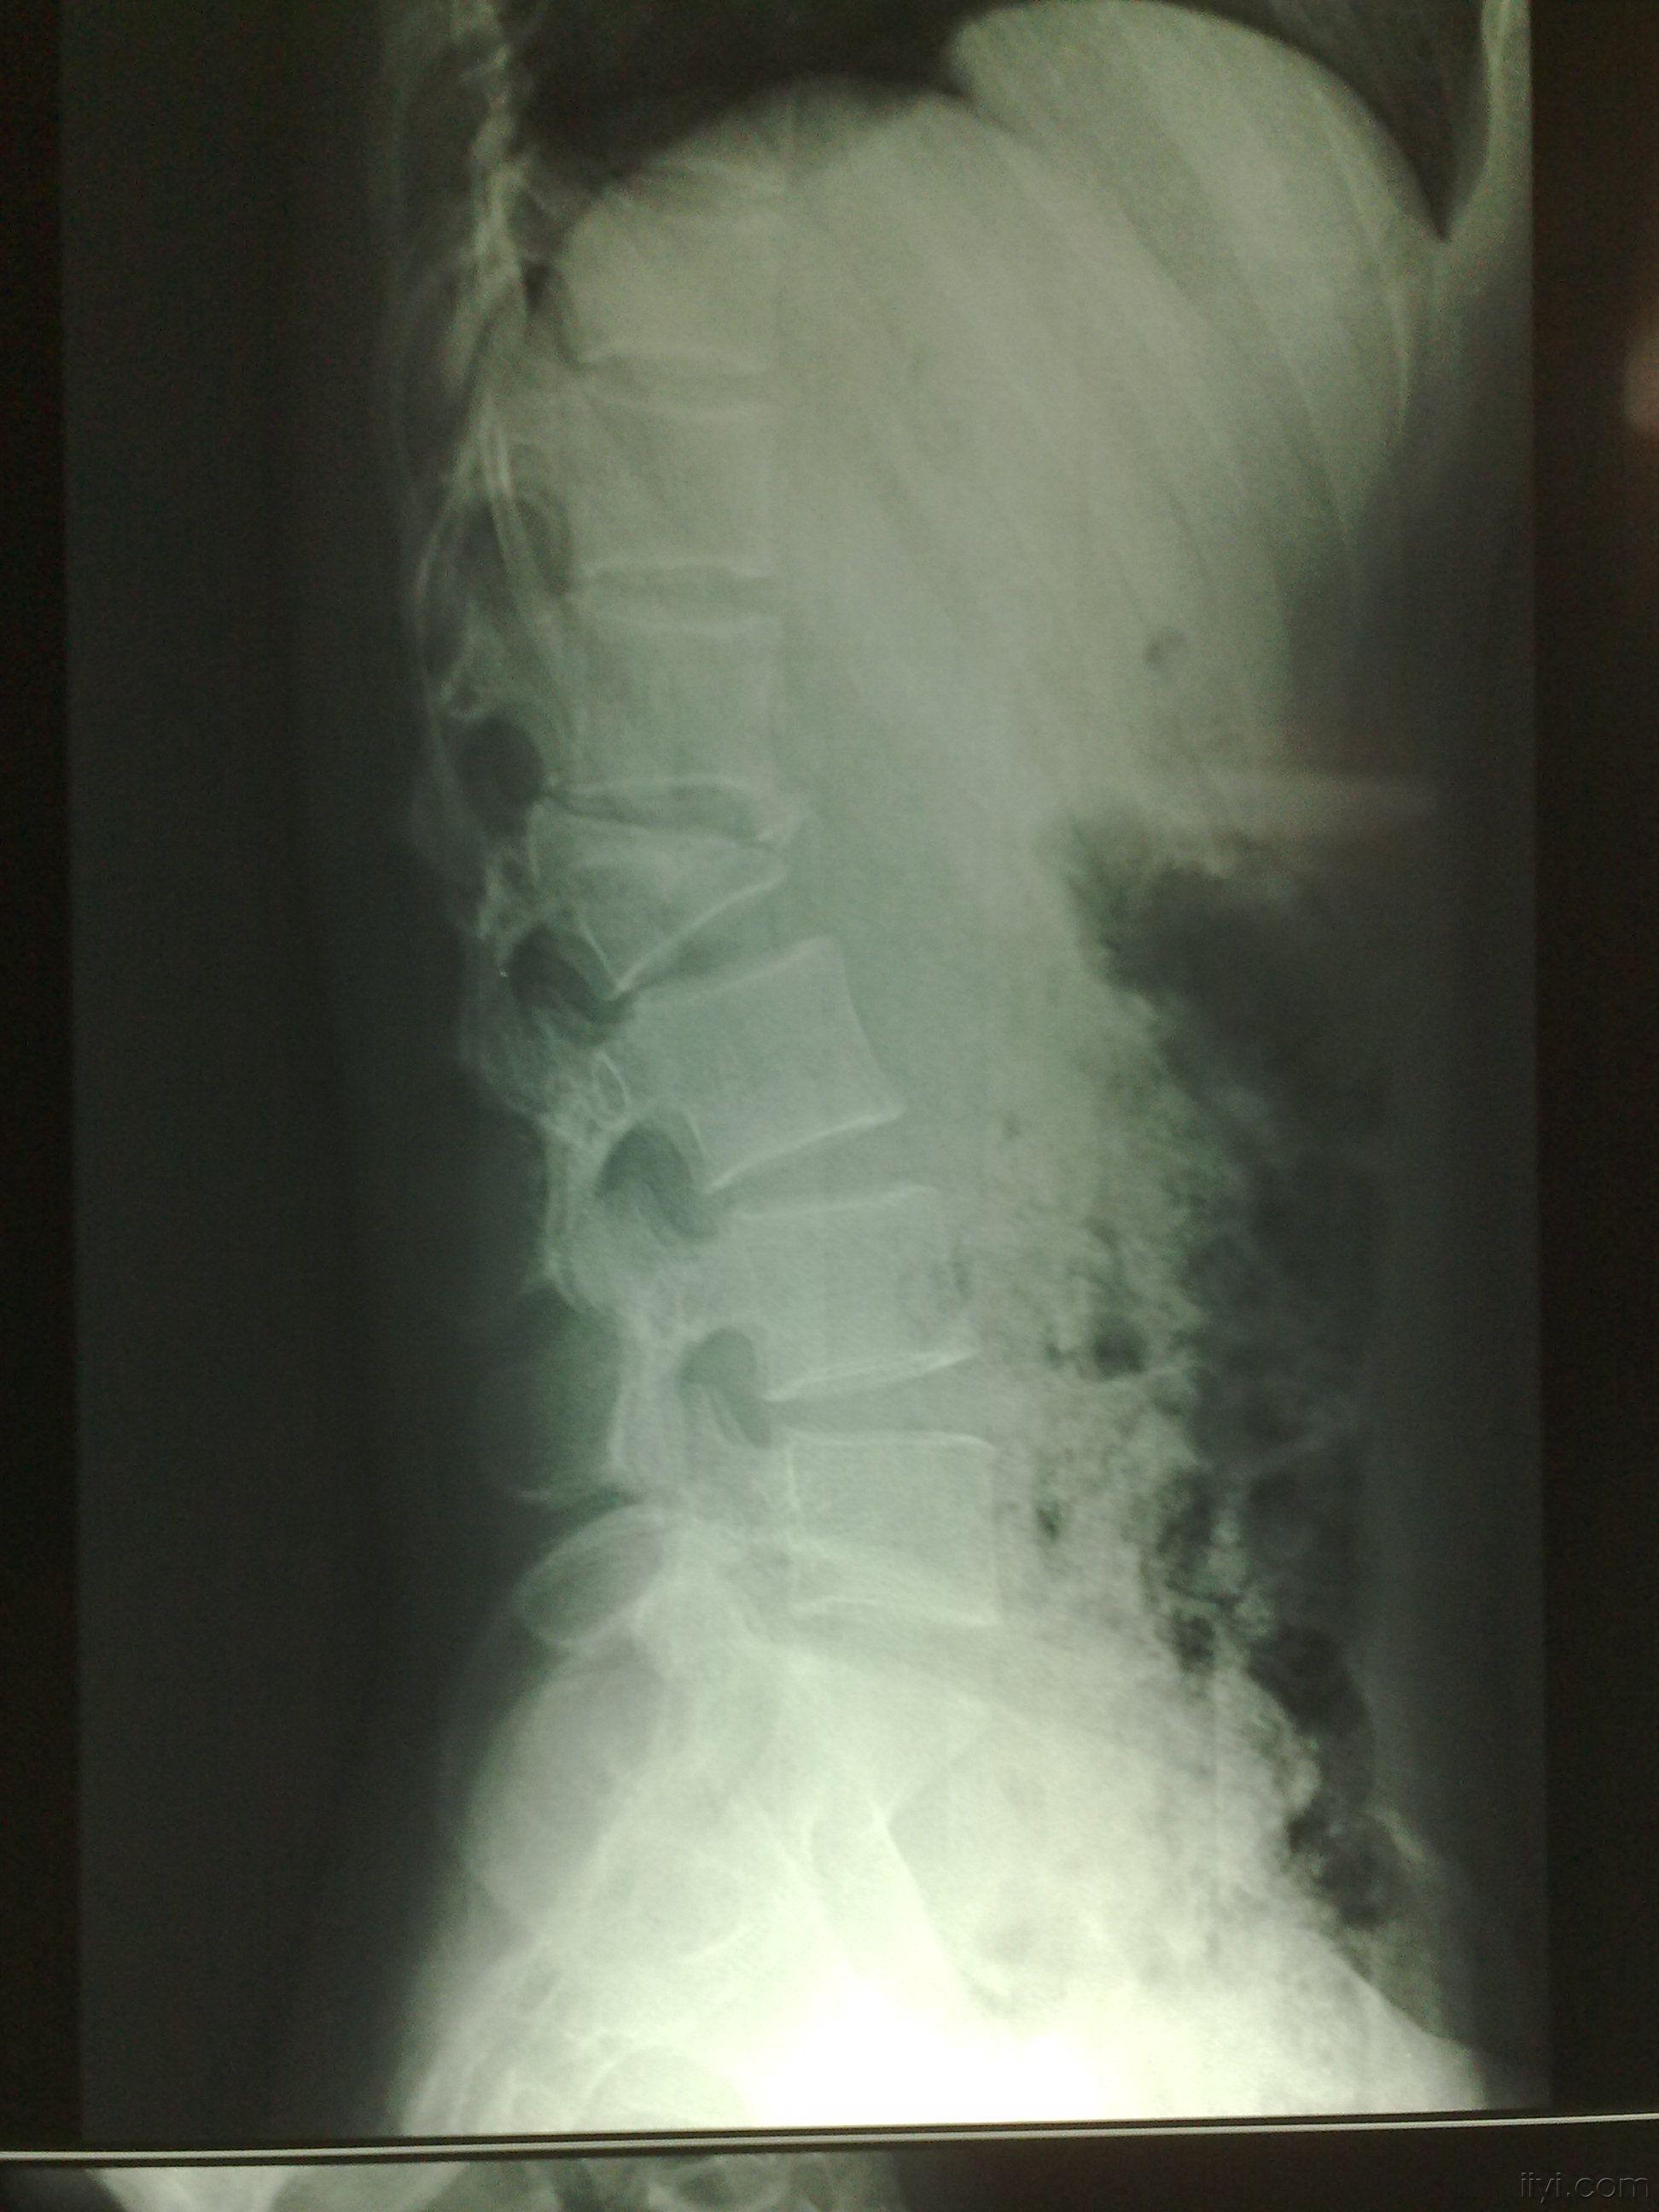

第二腰椎,第二腰椎怎么定位

腰椎影像解剖学

第二腰椎骨折

腰椎的解剖及腰部的层次解剖

第二腰椎段:下腹痛,腰酸痛,性机能减退